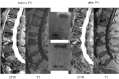

Osteoporotic vertebral compression fracture of L2 with absent bone marrow edema (BME) treated by percutaneous vertebroplasty (PV). Lateral STIR and T1-weighted MR images of the lumbar spine before and after PV. In the middle, lateral and anteroposterior radiographic images after PV.

Fig 3.

Osteoporotic vertebral compression fractures of L1 and L3 with partial bone marrow edema (BME) treated by percutaneous vertebroplasty (PV). Lateral STIR and T1-weighted MR images of the lumbar spine before and after PV. In the middle are lateral and anteroposterior radiographic images after PV.

Fig 4.

Osteoporotic vertebral compression fracture of L1 with full bone marrow edema (BME) treated by percutaneous vertebroplasty (PV). Lateral STIR and T1-weighted MR images of the lumbar spine before and after PV. In the middle, lateral and anteroposterior radiographic images after PV.